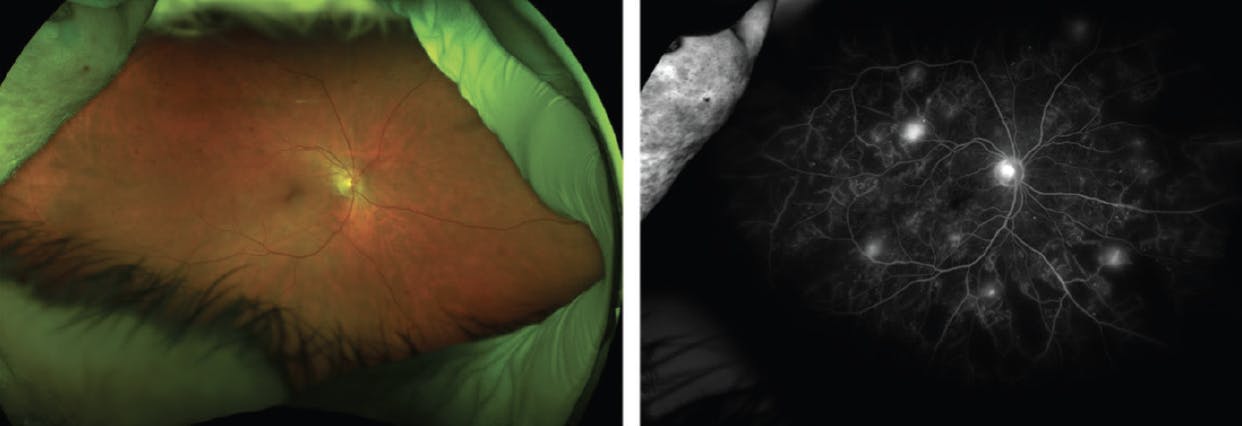

A 63-year-old woman was referred for a DR evaluation. Fluorescein angiography revealed several areas of neovascularization elsewhere (NVE) in each eye (Figure 3), and OCT imaging showed trace DME in each eye. VA was 20/20 OU, so I decided to treat both eyes with panretinal photocoagulation (PRP). This patient has done well for a year now while maintaining a VA of 20/20 with regression of the NVE in each eye.

<p>Figure 3. This 63-year-old woman with DR in each eye presented with NVE in each eye and subsequently underwent PRP in each eye, leading to the regression of the NVE.</p>

Figure 3. This 63-year-old woman with DR in each eye presented with NVE in each eye and subsequently underwent PRP in each eye, leading to the regression of the NVE.

Counseling patients on the risks of each option—anti-VEGF or PRP—for PDR is important, as is taking into consideration the patient’s systemic comorbidities and ability to follow up. Patients with PDR often miss appointments due to frequent medical appointments (eg, for dialysis) or hospitalization. Studies show that eyes that are lost to follow-up did better when treated with PRP compared with those treated with anti-VEGF injections alone.10